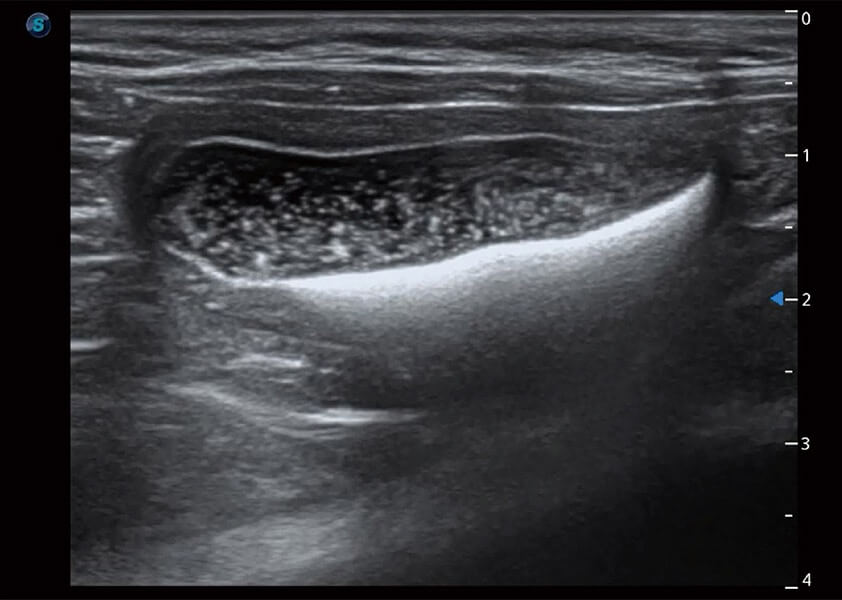

ProPet 60 作为一款高端台式动物超声设备,为动物医生的日常诊断提供了一系列贴合动物临床需求、解决临床实际问题的高级成像功能。凭借全系列高清探头,满足医生对腹部、心脏、生殖、浅表、肌骨等成像的所有需求,切实帮助您提升检查效率,提高诊断信心。

动物是人类最亲密的朋友和最值得信赖的伙伴。银河集团官网也一直致力于探索动物专用的超声影像解决方案。 全新推出的ProPet系列,是银河集团官网在动物超声影像智能化、专业化、精准化的一次跨越式革新。动物不能用言语来表述自己的不适,通过超声影像,ProPet系列搭建了动物医生与不同物种沟通的“桥梁”,为动物医生注入了“治愈之力”。